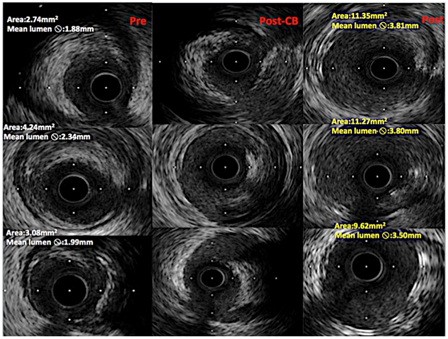

Coronary angiography revealed long, calcified > 40mm length lesion in right coronary artery proximal and middle part (Figure 1). Our decision was to treat this coronary lesion with BRS (Absorb BRS; Abbott Vascular, Santa Clara, CA, USA), following our centre plaque modification strategy, which is plaque modification before scaffold implantation using cutting or scoring balloon. In this case we used cutting balloon pre-dilatation 3.5x15mm 13 bars for each segment three times. Vessel dimensions were pre-analyzed with imaging methods to choose appropriate pre-dilatation balloon size. “PSP (Predilatation, Sizing, Post-dilatation) technique” that improves Absorb implantation is now widely described. Our centre following updated technique which is “IPSP (Imaging, Predilatation, Sizing, Postdilatation” technique. After plaque modification three BRS were implanted with total length 68mm. All scaffolds were implanted with small overlap to avoid uncovered gap which can provoke flow disturbances and possible future problems. Scaffold diameter was 3.5mm. An optimal scaffold apposition to vessel wall was achieved with non-compliant balloon 4.0x20mm. Post-dilatation was done with 15 bars in each segment. Mandatory for this intervention are imaging methods – intravascular ultrasound (IVUS) and optical coherence tomography (OCT). IVUS was performed before PCI, after plaque modification and after BRS implantation (Figure 2). OCT was performed after BRS implantation (Figure 3). Final angiography showed good result of procedure (Figure 4). Patient discharged next day on dual anti-platelet therapy for two years. Now patient reached six-month clinical follow-up with no cardiovascular events or bleeding.

Figure 2 IVUS cross-sectional images from pre-intervention (first colon from left), after plaque modification with cutting balloon (middle colon), after scaffold implantation (left side colon). In middle colon can seen vessel lumen dissections, made by cutting balloon. Lumen changes in diameters can be seen from left to right colons.